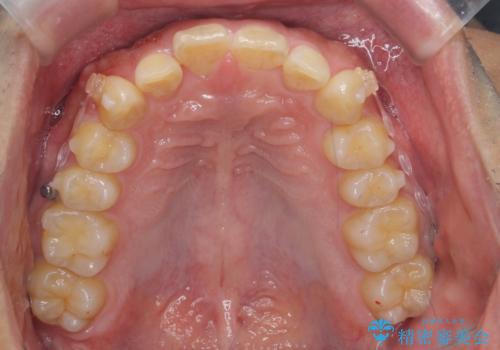

出っ歯を治したい 深いかみあわせ インビザラインで治療

- 前歯の前突を主訴に来院。

上の歯並びが前方にずれていました。

上顎は歯を抜かずに、奥歯を後ろに下げる治療を行っています。